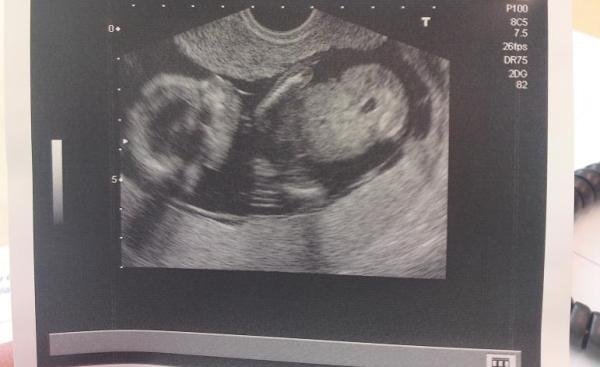

habe euch auch zwei Bildchen!!

Baby geht es super, ist zeitgerecht entwickelt. SSL ist jetzt bei 9,5 cm. und es war richtig aktiv, hat kaum ne Sekunde still gehalten. schließlich hat sie zwischen den Beinchen geschaut und siehe da, es war tatsächlich ein Zipfelchen zu sehen! wir bekommen also einen Jungen!!! war im ersten Moment überrascht, weil ich mich so auf ein Mädchen versteift hatte, aber wahrscheinlich auch nur deshalb weil ich mir im Grunde ein Mädchen gewünscht habe. in letzter Zeit hatte ich und auch mein Mann aber geträumt dass es ein Junge wird.